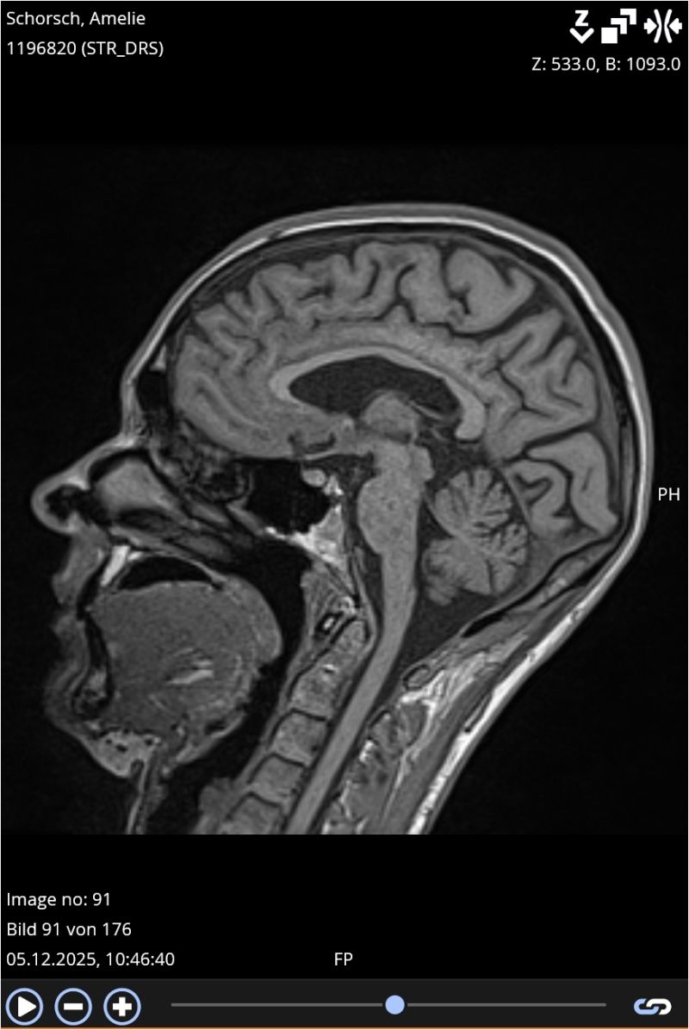

Diese Woche war ich mal wieder im MRT.

Ein Termin, der jedes Jahr ansteht.

Ein Termin, der rational „Routine“ ist – und emotional alles andere als das.

Diesmal: keine Aktivität.

In der sekundär progredienten MS (SPMS)

nimmt die klassische entzündliche Aktivität meistens ab,

man sieht seltener neue, aktiv entzündliche Läsionen, also „lodernde Feuer“.

* Das liegt daran, dass die SPMS oft durch Prozesse vorangetrieben wird, die im MRT weniger sichtbar sind, z. B. langsame axonale Schäden oder Mikroentzündungen.

Und trotzdem ist ein MRT ohne neue Aktivität ein gutes Zeichen, weil es bedeutet: Keine zusätzlichen Entzündungsherde, kein neuer akuter Schaden.